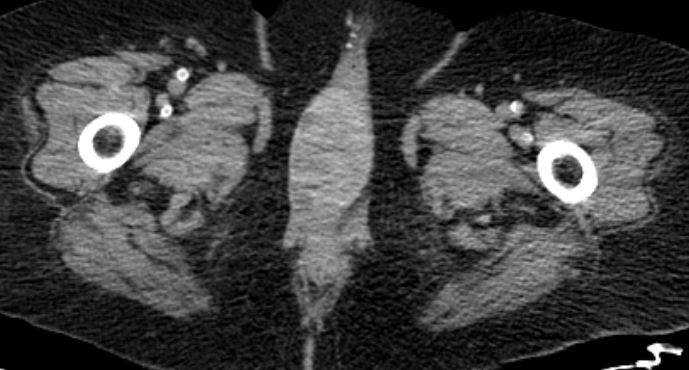

82-jährige Frau mit einem Leiomyosarkom der Vulva rechts pT2a N0 M0, V1, G2.

Klinik: Vulva-Tumor rechts. Der Tumor ist relativ glatt begrenzt und gut 5 cm groß; er ist auf dem absteigenden Schambeinast beweglich und reicht dicht bis an die Urethralöffnung heran.

Makroskopie: subepidermal gelegenes Leiomyosarkom. Zentral gelegen ein die Haut vorwölbender, 6,5 cm messender Tumor.

Hemivulvektomie rechts, R1-Resektion basal und medial. Brachytherapie.

8 Monate nach Primärtherapie auftreten von Knochenmetastasen. Kein lokales Rezidiv.